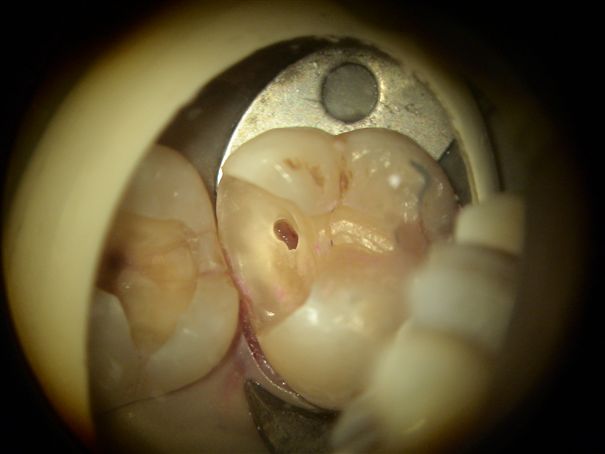

別の症例ですが、 レジンインレーを取り除くと、中に茶色みがかった色の虫歯が認められます。この虫歯の場合相当深くなっていることが予想されます。 |

虫歯を感染に取り除くと、は本来の色になりましたが、神経が露出しそうな状態です。 |